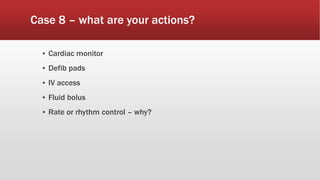

This document discusses various cases of collapse and syncope. It defines collapse as transient loss of consciousness with loss of postural tone and full recovery. Syncope is defined as loss of postural tone with or without loss of consciousness and full recovery. It then discusses the multiple potential causes of collapse and syncope including toxicological, cardiac conduction abnormalities, structural cardiac issues, autonomic dysfunction and more. It then goes through 9 case examples, discussing important questions to ask, potential tests and interventions for each case.